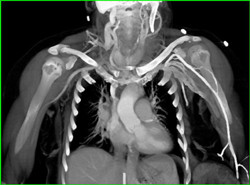

Diagnosis

Loeys-Dietz With Ectatic Vessels